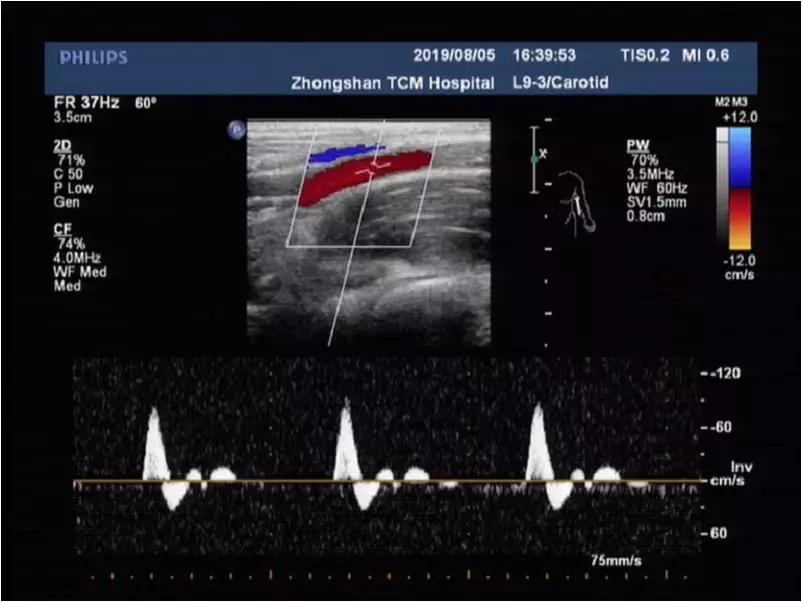

自然体位:上肢动脉流速正常,高阻力